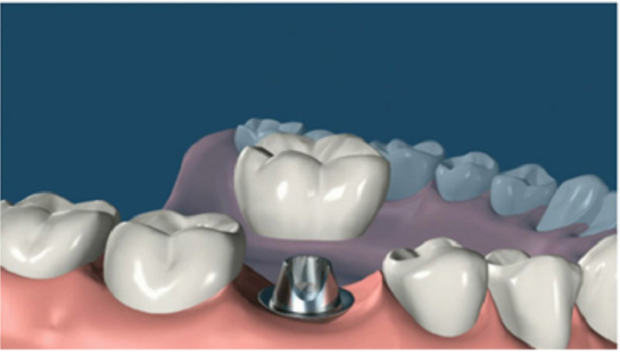

7. 覆蓋義齒:兩至三周待軟組織成型后,就可以把愈合基臺(tái)換成基臺(tái)佩戴種植牙冠了;至此種植牙全部流程都已全部完成。